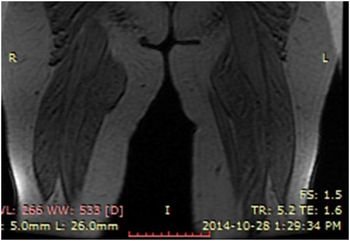

74-year-old female presented with multiple, soft swellings around the knees and upper thighs.